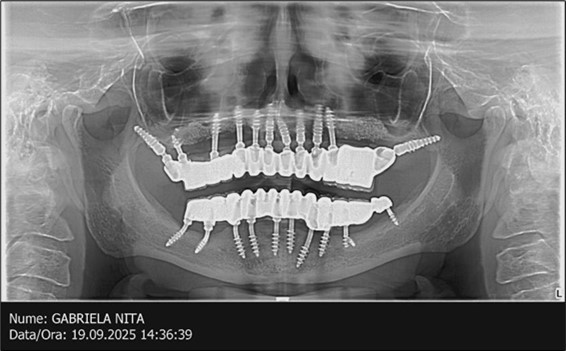

The results of rehabilitation treatment with corticobasal and compressive implants with a polished surface after the failure of two stage implants were highlighted over a period of 3 years and 3 months as being very good (Figure 14, Figure 15), with the patient completing a satisfaction survey in this regard. Certainly, it is necessary to continuemonitoring these results in the long term.

The following aspects were evaluated regarding the results:

-Patient satisfaction related to aesthetics, mastication, and phonation.

-Hygiene capability at the junction between the prosthetic restoration and implants.